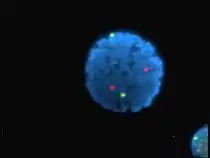

Imagerie en épifluorescence de trois composantes d'un cellule cancéreuse humaine en cours de division. L'ADN apparaît bleu, une protéine dite INCENP apparaît en vert, et les microtubules en rouge. Chaque fluorophore a été imagé séparément, avec une longueur d'onde d'excitation spécifique et des filtres, puis une image a été recomposée, à partir des photos prises par la caméra CCD.